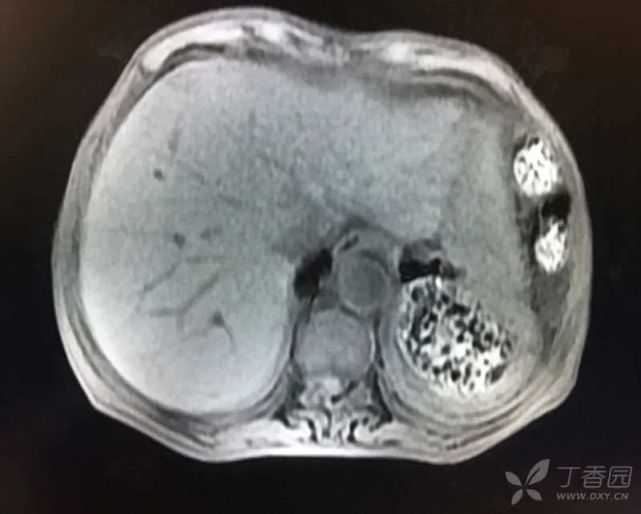

2016 年 2 月患者因「腹胀腹痛 3 d」入住我院普外科。查上腹部 CT 示:脾大、脾破裂、腹腔积液、积血(图 5)。行脾切除术,术后恢复顺利,很快出院。住院期间首次发现肝酶升高:生物化学:ALT 22 U/L,AST 28 U/L,ALP 190 U/L,GGT 323 U/L,TBil 6.6 μmol/L,DBil 2.7 μmol/L,CREA:66 μmol/L。

图片

(图 5 上腹部 CT 图)